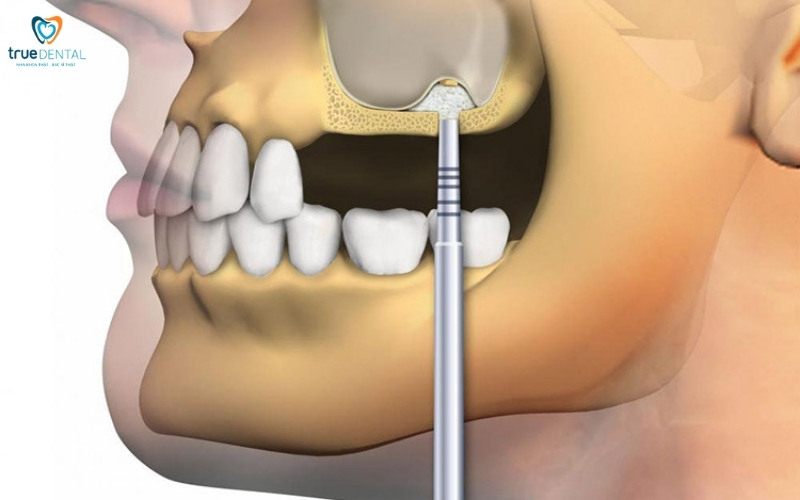

Kỹ thuật nâng xoang hàm

Cấy ghép implant có ảnh hưởng đến xoang hàm không? – Sẽ không nếu thực hiện đúng kỹ thuật. Trong một số trường hợp bác sĩ có thể nâng xoang hàm. Đây là giải pháp được áp dụng khi chiều cao xương không đủ. Kỹ thuật này nhằm mục đích tạo thêm không gian và thể tích xương ở vùng đáy xoang để cấy trụ Implant dài hơn.

- Nâng xoang kín: Áp dụng cho trường hợp thiếu xương nhẹ (còn khoảng 6-8mm xương). Bác sĩ nâng sàn xoang nhẹ nhàng thông qua lỗ khoan cấy Implant, sau đó bơm vật liệu ghép xương vào khoang nhỏ bên dưới màng xoang. Kỹ thuật này ít xâm lấn và thường kết hợp cấy Implant cùng lúc. Bằng cách này, bác sĩ sẽ giúp bạn bổ sung đủ mật độ xương, giúp quá trình trồng răng implant diễn ra thuận lợi và không còn lo lắng cấy ghép implant có ảnh hưởng đến xoang hàm không.